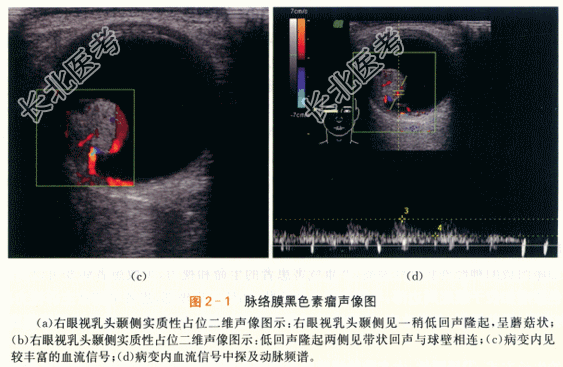

- [材料题] 患者,男性,52岁,因“右眼视力逐渐下降半年.眼前黑影伴视物变形1周”就诊。体格检查:患者视野检查示蓝色视野缺损大于红色视野缺损。特殊检查:眼底检查示右眼玻璃体混浊。颞侧可见脉络膜实性隆起,呈棕褐色,表面有出血。隆起物周边视网膜呈青灰色隆起。影像资料如下:

- 1、若患者诊断为脉络膜黑色素瘤,其声像图